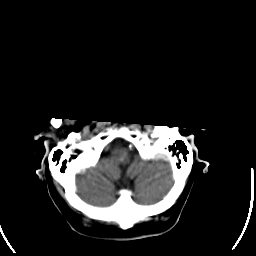

Stroke CT #2 -- Slice #2

[Home][Help][Clinical] Slice 2